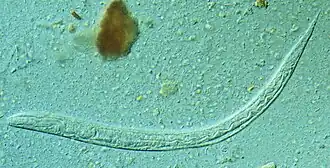

![]() Larva del Strongyloides stercoralis | ||

La estrongiloidiasis es una parasitosis intestinal tisular, causada por el nematodo Strongyloides stercoralis. Es una enfermedad humana importante en personas inmunodeficientes.